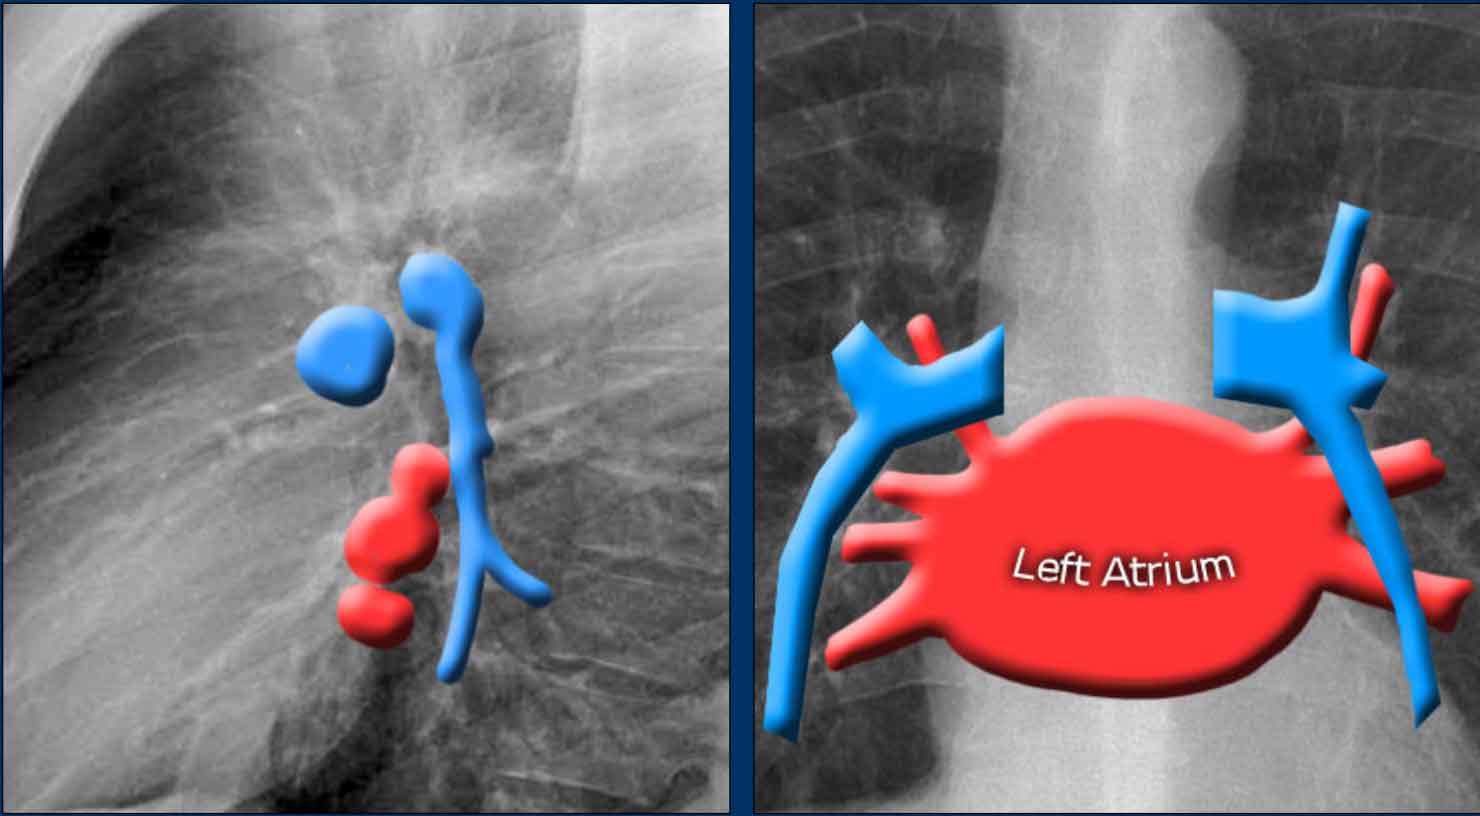

Left Atrium (LA)

It is the most posterior cardiac chamber and it receives oxygenated blood from the pulmonary veins, which enter the left atrium almost horizontally. The left atrial appendage is occasionally visible as a small outpouching just below the pulmonary trunk (best seen on lateral view).

Radiographic signs of left atrial enlargement:

• PA view: Bulging of the upper right heart border and widening of the carinal angle due to splaying of the main bronchi.

• Lateral view: Bulging of the posterior-superior cardiac contour.